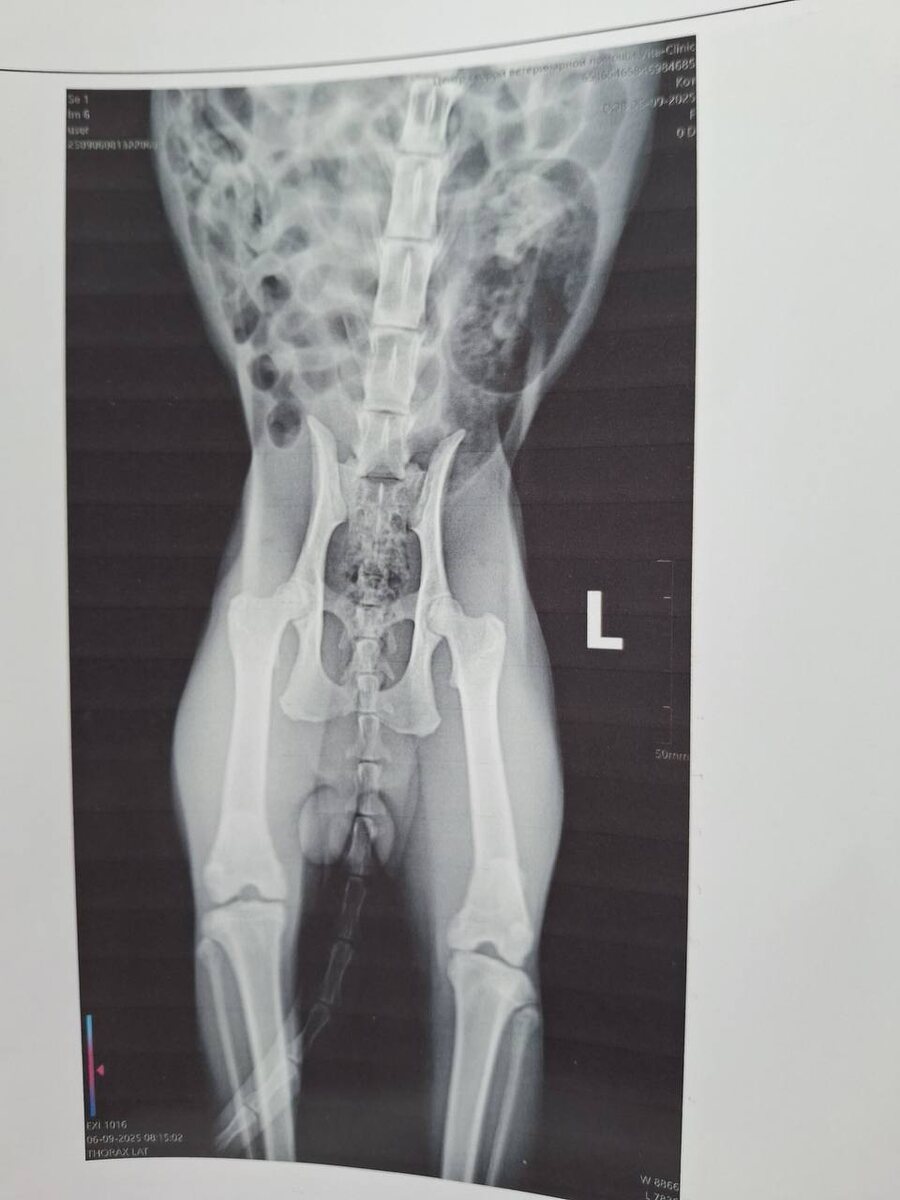

В субботу мне позвонили ребята, ехали проездом через Хабаровск с собаками на соревнования, подобрали кота сбитого на трассе, возле деревни, довезли до Вита клиники, попросили принять, в семь вечера уехали дальше. Кот тяжёлый, перелом черепа в трех местах, плюс осколок, трогать нельзя, перевозить пока тоже, взяли на приют, девать его некуда🤷‍♀️так что у нас новый подопечный без имени

Кот тяжёлый, перелом черепа в трех местах, плюс осколок, трогать нельзя, перевозить пока тоже, взяли на приют, девать его некуда🤷‍♀️так что у нас новый подопечный без имени